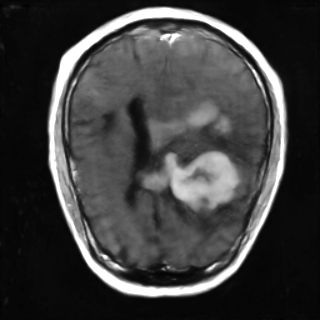

This article presents a novel undersampled magnetic resonance imaging (MRI) technique that leverages the concept of Neural Radiance Field (NeRF). With radial undersampling, the corresponding imaging problem can be reformulated into an image modeling task from sparse-view rendered data; therefore, a high dimensional MR image is obtainable from undersampled $k$-space data by taking advantage of implicit neural representation. A multi-layer perceptron, which is designed to output an image intensity from a spatial coordinate, learns the MR physics-driven rendering relation between given measurement data and desired image. Effective undersampling strategies for high-quality neural representation are investigated. The proposed method serves two benefits: (i) The learning is based fully on single undersampled $k$-space data, not a bunch of measured data and target image sets. It can be used potentially for diagnostic MR imaging, such as fetal MRI, where data acquisition is relatively rare or limited against diversity of clinical images while undersampled reconstruction is highly demanded. (ii) A reconstructed MR image is a scan-specific representation highly adaptive to the given $k$-space measurement. Numerous experiments validate the feasibility and capability of the proposed approach.